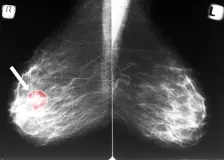

Systémy s umělou inteligencí dokážou s mimořádnou přesností třídit mamografické snímky a upozornit na podezřelé nálezy.

Lékař: Díky AI se podaří zachytit asi o 15 procent nádorů prsu víc než bez ní

Praha - Použití umělé inteligence (AI) při preventivním vyšetření prsu zvyšuje záchyt rakoviny asi o 15 procent. Odhalí i malé nádory, které se pak lépe léčí. Na tiskové konferenci Oborové zdravotní...